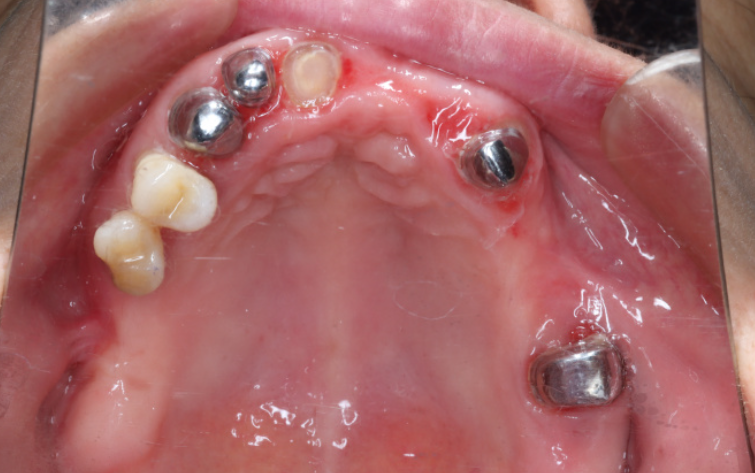

套筒冠义齿收费标准受材料选择、修复范围、医疗机构类型等多种因素影响,不同地区的收费差异明显。www.59w.net目前市场上,单颗套筒冠义齿价格从4500元起,全口套筒冠无挂钩假牙34000元起,具体费用需结合患者口腔条件、所选材料及机构报价较终确定。

总的来说,套筒冠义齿收费标准区间较大,单套价格从3800元起,全口价格34000元起,半口价格18000元起。具体费用会因材料选择、修复范围、附加治疗及机构差异而变化。建议患者根据自己的口腔条件和预算,选择正规的口腔机构,面诊后确定适合的方案,不要只看价格而忽略修复疗效和长期稳定性。